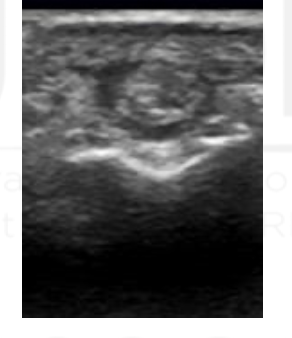

What view is this?

PIP

Synovium

Extensor Tendon

Proximal Phalanx

Middle Phalanx